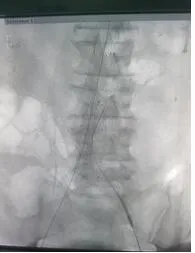

胸心外科姜永红副主任接诊该患者后,考虑患者病情危急,随时有腹主动脉瘤破裂危险,立即上报医务科,启动MDT团队。次日胸心外科团队在介入科及相关科室支持下成功完成医院首例腹主动脉瘤覆膜支架腔内隔绝术。

9月17日,手术顺利进行,李某身体内的“炸弹”危机随之解除,家人悬着的心也放下来了。姜永红介绍,主动脉瘤不是真正的动脉肿瘤,而是各种原因造成的主动脉局部或多处扩张,膨大呈瘤样改变称为主动脉瘤。主动脉瘤通常与老龄化、高血压、动脉粥样硬化、遗传、外伤、感染或其他损伤动脉壁强度的各种因素有关。日积月累,动脉壁日益薄弱,动脉瘤突然破裂可导致病人突然死亡。